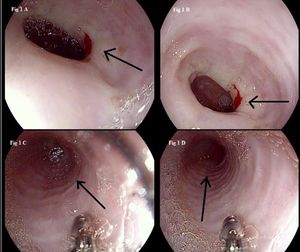

Eosinophilic esophagitis is often misdiagnosed as gastroesophageal reflux disease but does not respond to acid suppression therapy. Here, a close-to-textbook case.